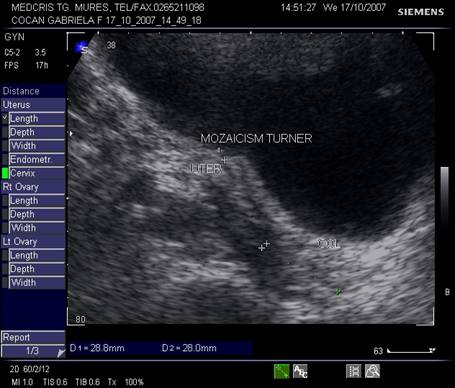

Fig. nr. 350.Uter infantil la o pacienta cu mozaicism Turner ( lungimea colului egala cu cea a corpului uterin ) la ecografia abdominala in sectiune sagitala